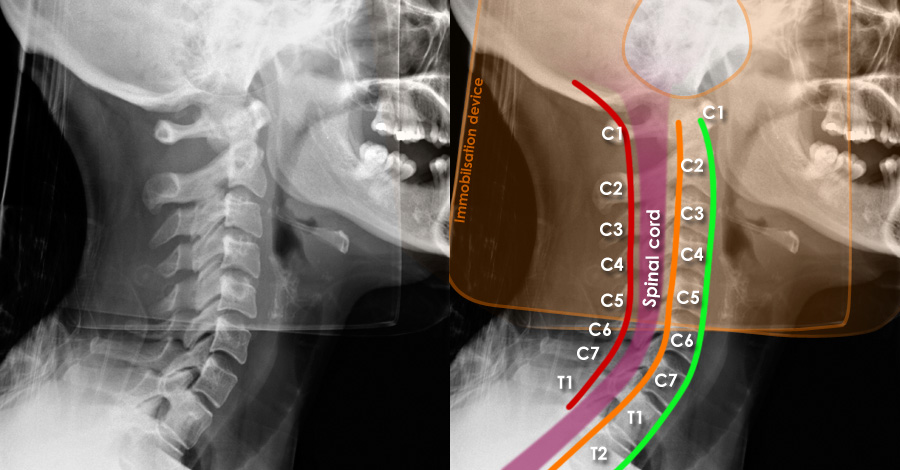

A CT scan revealed a catastrophic retropulsion of the C5 vertebral body—meaning it had fractured and shifted backward into the spinal canal, placing intense pressure on the spinal cord. The posterior section of the C6 vertebra was also fractured.

But here’s where the case baffled experts: none of the stabilizing structures of the spine—no facet joints, no pedicles, no ligaments—were damaged. This wasn’t supposed to happen. Current spinal injury classification systems, like Allen & Ferguson, SLIC, or AO Spine, are based on predictable patterns of failure. Arun’s injury didn’t match any of them.